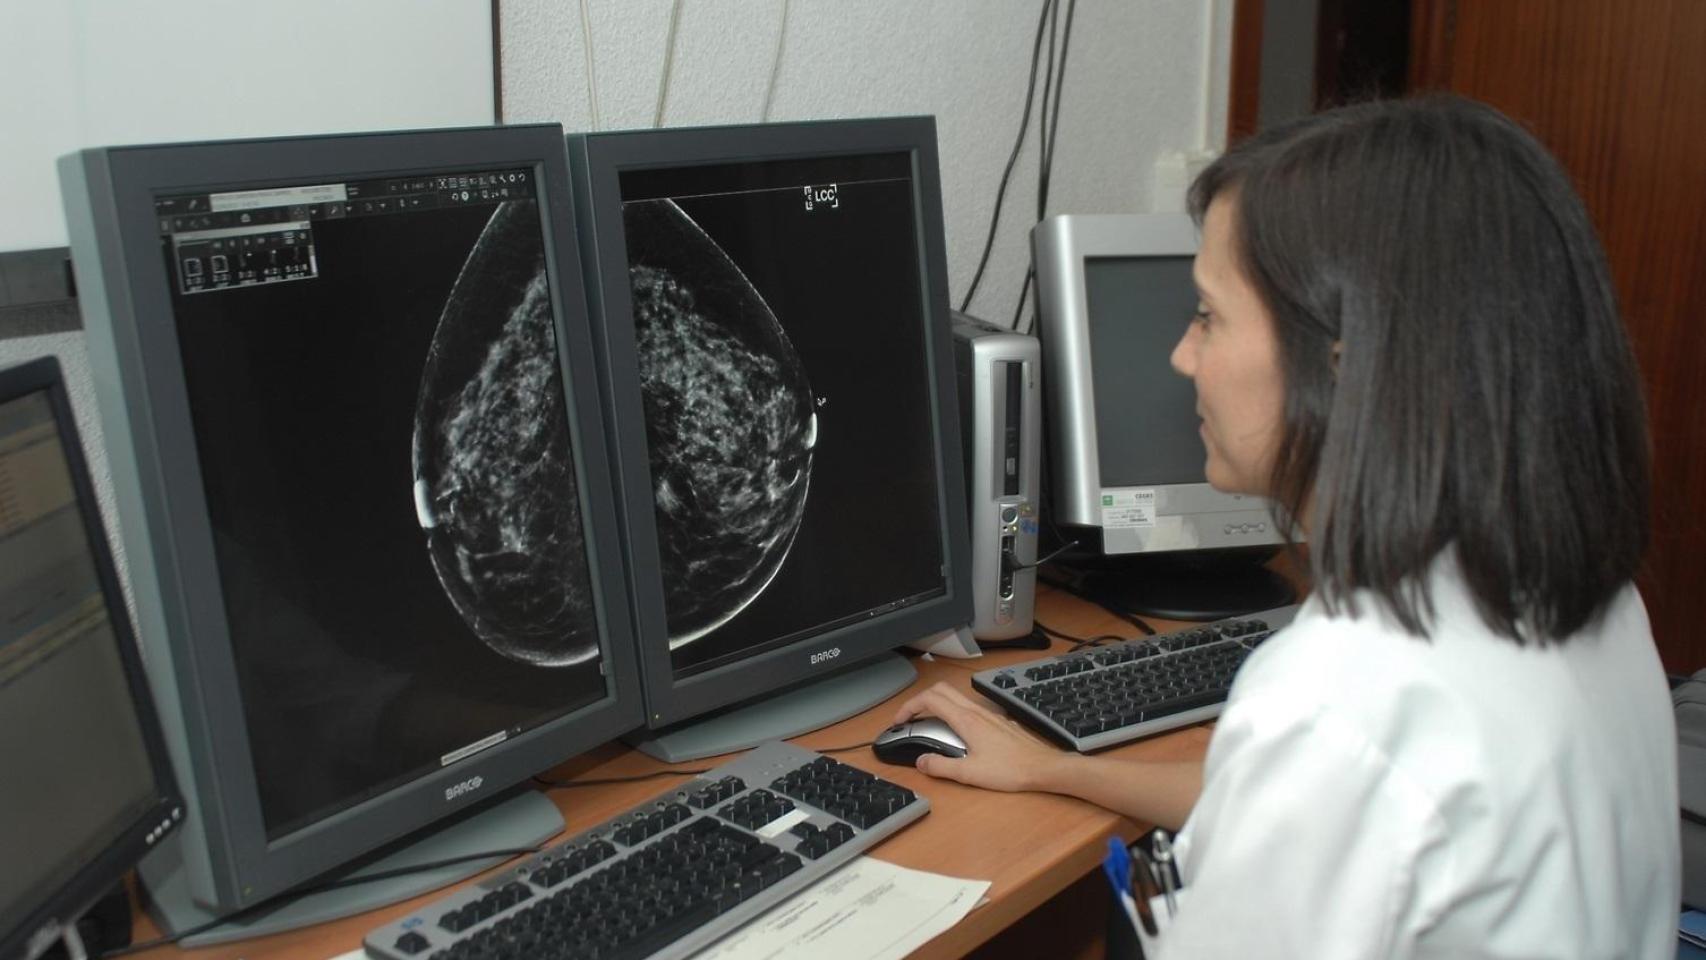

Los retrasos en el diagnóstico de los screening de cáncer de mama en Andalucía son terribles y extremadamente graves.

La noticia ha hecho saltar las alarmas. Y no sólo en esta comunidad autónoma, sino en todo el país.

De hecho, el Ministerio de Sanidad ha solicitado los datos de los indicadores de control y seguimiento de los tres screening de cáncer que hacemos en nuestro sistema sanitario público (mama, colon y cérvix), lo que parece razonable y normal ante la preocupación que suscita el tema.

Y, por lo que parece, lo hacemos mal.

Pero los sindicatos ya se han salido con la suya y la Junta va a incrementar la inversión pública con doce millones ad hoc para contratar más personal médico y técnico destinado a solucionar los problemas de las pacientes del screening de mama.

Cientos de andaluces se concentran en las puertas del SAS por los fallos en el cribado de cáncer de mama.